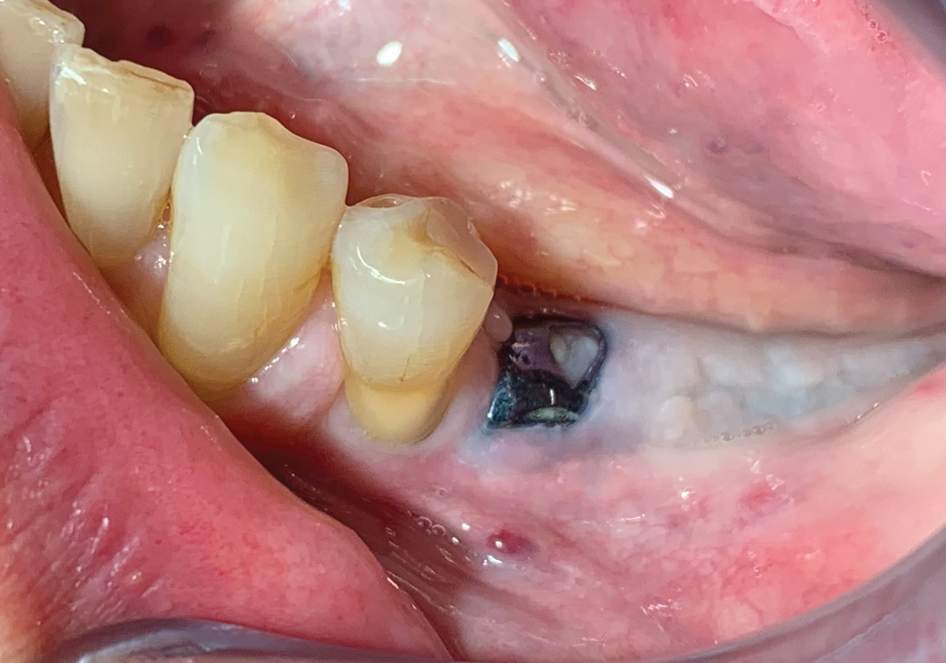

Fig 6. Clinical observation at re-entry (5.5 months after grafting) showing exposure of the mesh.

Figure 6

Clinical follow-ups at 2 and 7 days post- surgery were performed and did not show any complications. Sutures were removed after 14 days. During the healing period, the mesh became slightly exposed (Figure 6), and the patient was instructed to clean the exposed area with chlorhexidine on a cotton tip (twice a day) to keep the area clean.